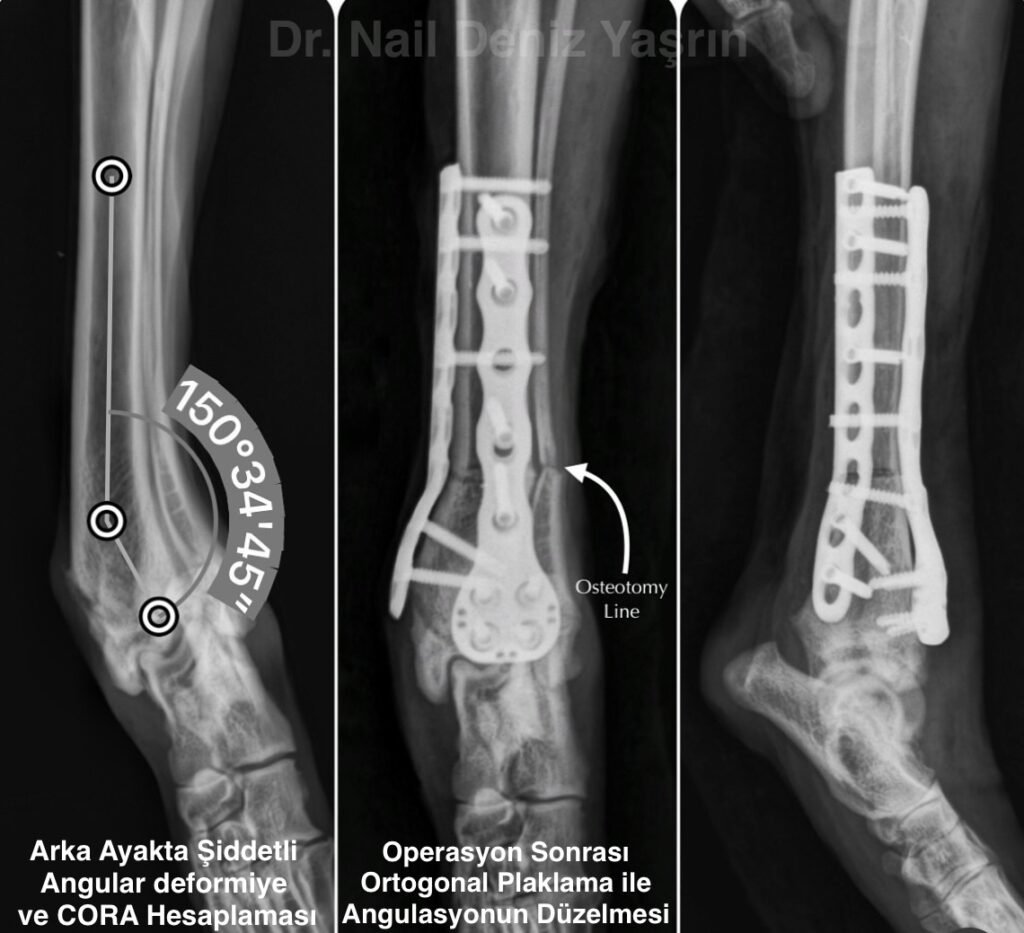

1. Eklemi Koruyan Cerrahiler: Korektif Osteotomiler

Eklem yüzeyi henüz bozulmamışsa, kemik açısını düzelterek yük dağılımını optimize ederiz.

- Yöntem: Kemiğe yapılan kontrollü kesiler (osteotomi) ve plak-vida sistemleri ile açının düzeltilmesi.

- Amaç: Eklem biyomekaniğini düzelterek, hastanın kendi eklemini ömür boyu kullanmasını sağlamak ve protez ihtiyacını ortadan kaldırmaktır.